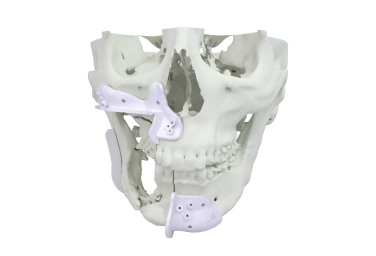

Cirurgia Reconstrutiva

Guias personalizados para coleta de enxertos ósseos no tamanho e ângulos exatos e para ressecção de tumores no local correto. Placas personalizadas, standard e parafusos apropriados para reconstrução precisa.